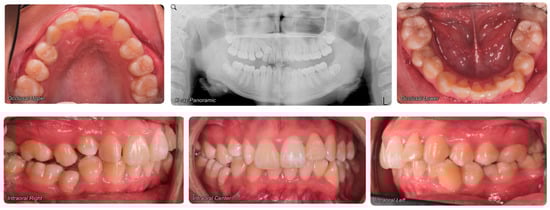

- Evaluation of impacted teeth, a common indication of CBCT in orthodontics. The advantages of CBCT include assessment of the tooth location and position, the stage of development, and status of adjacent teeth. CBCT is justified in these cases, because CBCT has the capability of evaluating the impacted teeth and adjacent structures more accurately than 2D conventional imaging. The benefit–risk ratio is favorable, especially if the CBCT volume is collimated to the impacted tooth. Figure 1, Figure 2, Figure 3 and Figure 4 show an example of impacted maxillary canines, and their proximity to the maxillary lateral incisors. Figure 1 shows an intraoral photograph. The benefit of CBCT acquisition in this case includes the ability to visualize the canines and the lateral incisors in three dimensions, which can be visualized in Figure 2 and Figure 3. In this case, the maxillary right lateral incisor exhibited external root resorption, a finding that would be difficult to see on a conventional 2D panoramic radiograph. Figure 4 shows a Maximum Intensity Projection of a panoramic view derived from the CBCT volume. This unique view is free of magnification, distortion, ghost images, and overlaps frequently seen in conventional 2D panoramic radiography.